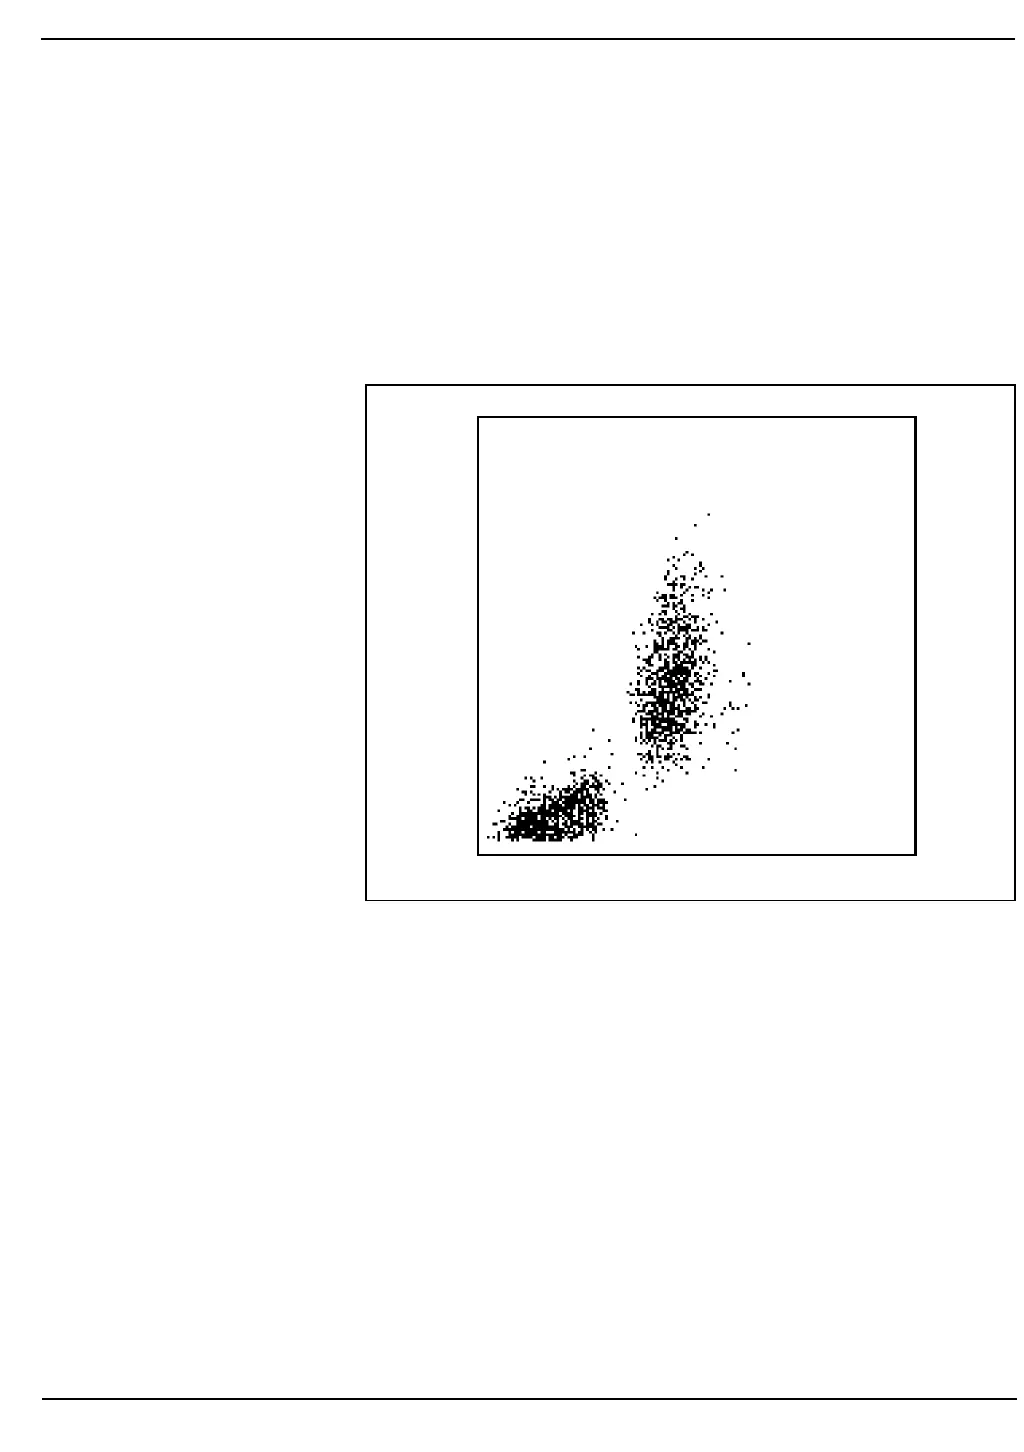

Two populations of cells are clearly seen on the display. The

mononuclear cells fall in the cluster in the lower left corner of the

scatterplot and the polymorphonuclear cells fall in the cluster above and

to the right of them.

The instrument uses a dynamic threshold to determine the best separation

between the two populations. Each cell is then identified as a MONO or a

POLY. Once each cell is identified, it retains this classification no matter

where it appears on other scatterplots.

Figure 3.4: Mononuclear-Polymorphonuclear Scatter